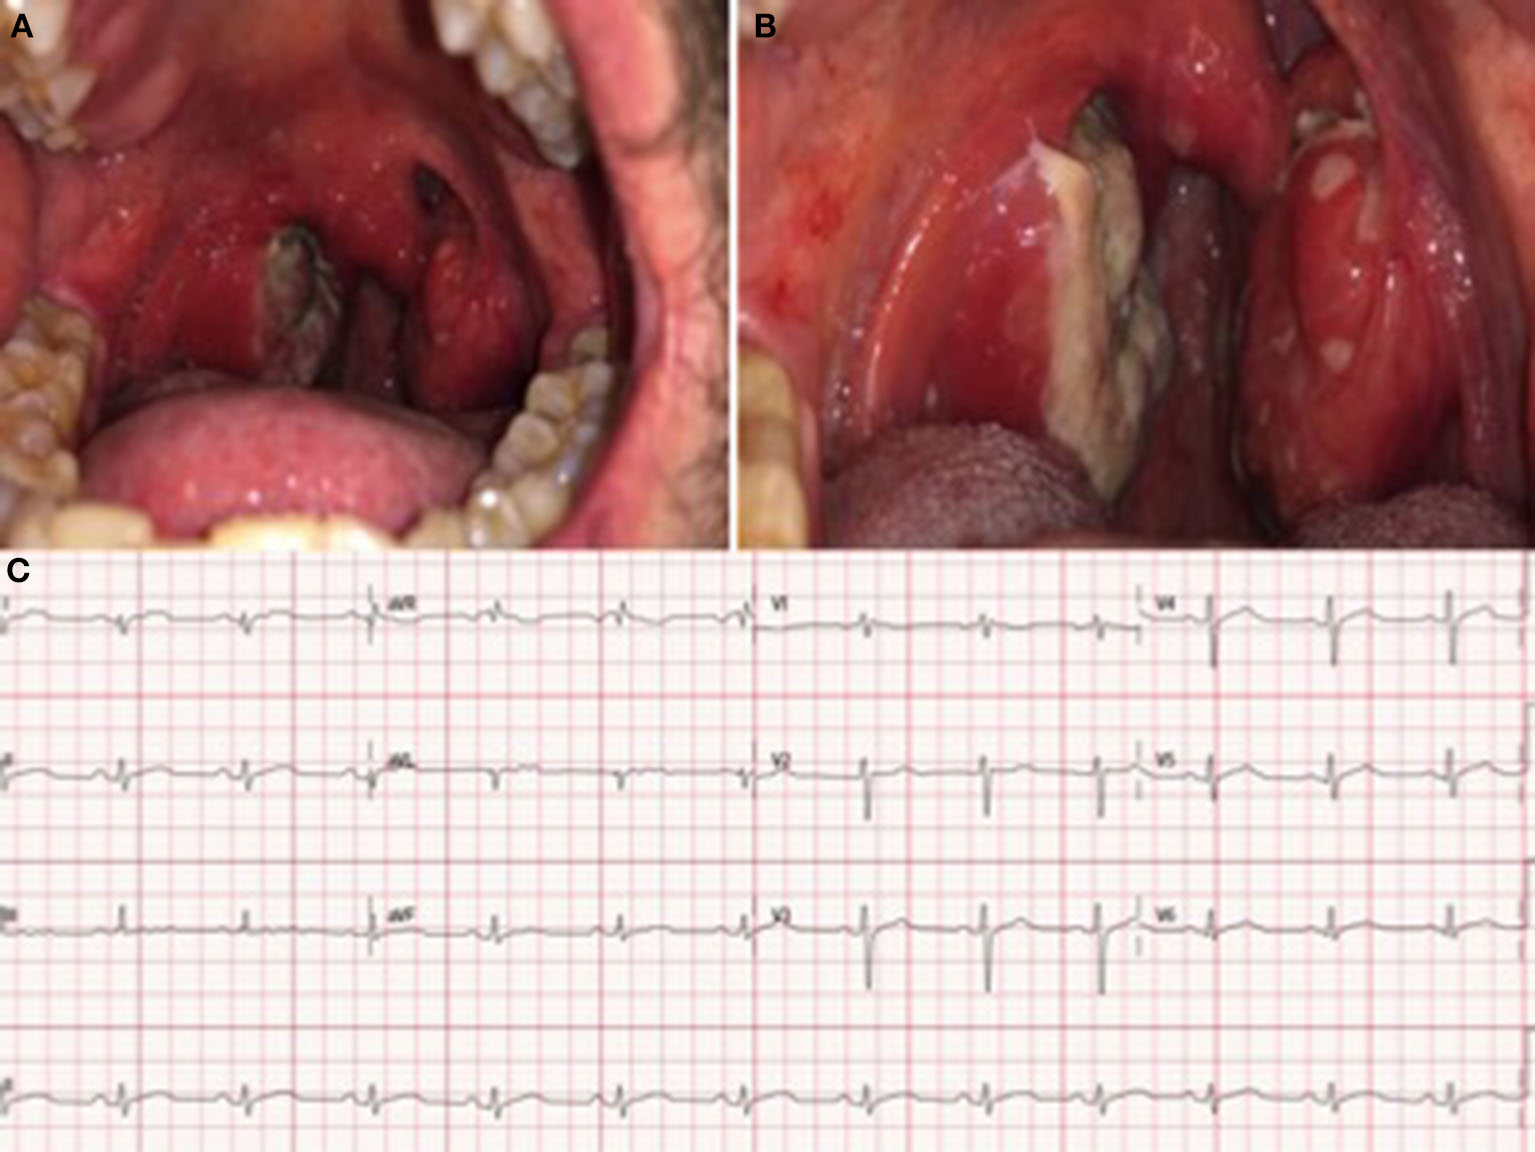

The physical exam revealed swollen tonsils and uvula. Multiple coalescing ulcerations covered the right tonsil with a necrotic base and confluent lesions, which showed a necrotic center and white margins (Figure 1A). No anogenital or skin lesions were present at this initial visit. During his stay at the hospital, a small number of millimetric umbilicated pustules with an erythematous base on the trunk and the proximal region of the limbs also appeared (Figure 1B).

Figure 1

Skin lesions (A, B), chest x-ray (C) at admission and electrocardiogram at admission (D). At admission, the electrocardiogram revealed sinus rhythm with diffuse ST elevation with upward concavity in leads (I, II, III, AVF, V4, V5, and V6) and diffuse depressed PR segment.

As potential HMPXV infection complications (systemic involvement and myocardial damage) occurred in this patient, requiring hospitalization, tecovirimat was requested from a drug agency. Following the Infectious Diseases Department's instructions, the treatment started 48 h after admission: 600 mg of oral Tecovirimat every 12 h for 14 days. No adverse events were reported. During his stay at the hospital, the previous electrocardiographic findings became normal (Figure 4A), whereas the oropharyngeal lesions increased in size and coalesced into large ulcerations located on both tonsils and the uvula (Figures 4B, C).

Figure 4

(A) Enlargement and coalescence of oral ulcerations on the tonsils and uvula 48 and 96 h after the diagnosis, respectively (B). (C) Electrocardiogram at discharge: Sinus rhythm without significant findings.